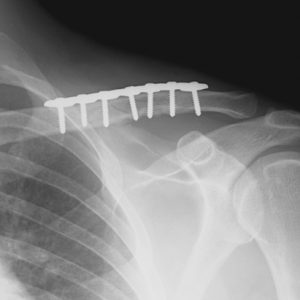

clavicula